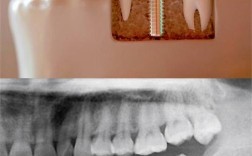

种植牙是目前修复缺失牙齿最理想的方式之一,它模拟了天然牙的结构(牙根+牙冠),对于“残牙”是否可以种植牙,主要取决于以下几个关键因素:

- 拍摄X光片: 根尖片、曲面断层片(全景片)。

- 拍摄CBCT(锥形束CT): 这是评估骨量(高度、宽度、密度)、神经血管位置、残牙状况的金标准,对制定精确的种植计划至关重要。

- 种植体植入手术: 在局麻下,将种植体(人工牙根)植入牙槽骨中。